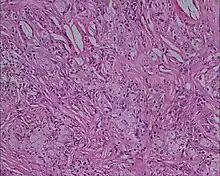

Xanthoma tuberosum

Xanthoma tuberosum (also known as tuberous xanthoma) is characterized by xanthomas located over tuberosity of the joints.[2]: 530